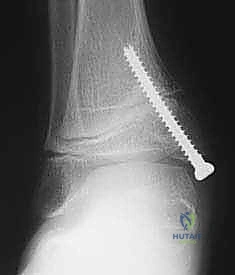

2. التصوير الشعاعي المتقدم:

لا يكتفي الدكتور هطيف بالفحص السريري، بل يتم إجراء صور أشعة سينية (X-rays) للقدم والكاحل أثناء وقوف الطفل (تحمل الوزن). يتم قياس زوايا دقيقة جداً لتقييم مدى الانحراف، مثل زاوية الساق والعقب (Tibiocalcaneal angle) وزوايا المفاصل الأخرى.

تُعد تقنية "تعديل النمو الموجه" (Guided Growth / Hemi-epiphysiodesis) واحدة من أعظم الابتكارات في جراحة عظام الأطفال الحديثة. بدلاً من إجراء جراحات قطع عظمي كبرى ومعقدة (Osteotomies) تتطلب فترة تعافي طويلة وجبساً لشهور، تعتمد هذه التقنية على مبدأ عبقري: تسخير قوة نمو الطفل الطبيعية لتصحيح التشوه.

يشبه الأمر تماماً تقويم الأسنان. يقوم الأستاذ الدكتور محمد هطيف بتركيب شريحة معدنية صغيرة جداً (تُعرف بشريحة الـ 8-Plate أو شريحة الشد) على الجانب الداخلي (الأسرع نمواً) من مركز النمو في أسفل عظمة الساق. هذه الشريحة تعمل كمكبح لطيف؛ فهي تبطئ النمو في الجانب الداخلي، بينما تسمح للجانب الخارجي بالاستمرار في النمو بشكل طبيعي. بمرور الأشهر، وبفضل استمرار نمو الطفل، "يُعدّل" الكاحل نفسه تدريجياً ويستقيم محوره تماماً.

- الأشهر من 1 إلى 6: هذه هي مرحلة "السحر الطبي". خلال هذه الأشهر، ومع نمو الطفل، يبدأ الانحراف بالتلاشي تدريجياً. تتم جدولة زيارات دورية لعيادة الدكتور هطيف لإجراء أشعة سينية ومراقبة تقدم التصحيح.

- إزالة الشريحة: بمجرد أن يستقيم الكاحل ويصل إلى الزاوية الطبيعية المثالية (غالباً بعد 6 إلى 12 شهراً)، يتم إجراء عملية جراحية صغرى وسريعة جداً لإزالة الشريحة والمسامير، ليُترك الطفل بقدم سليمة ومفصل طبيعي تماماً.